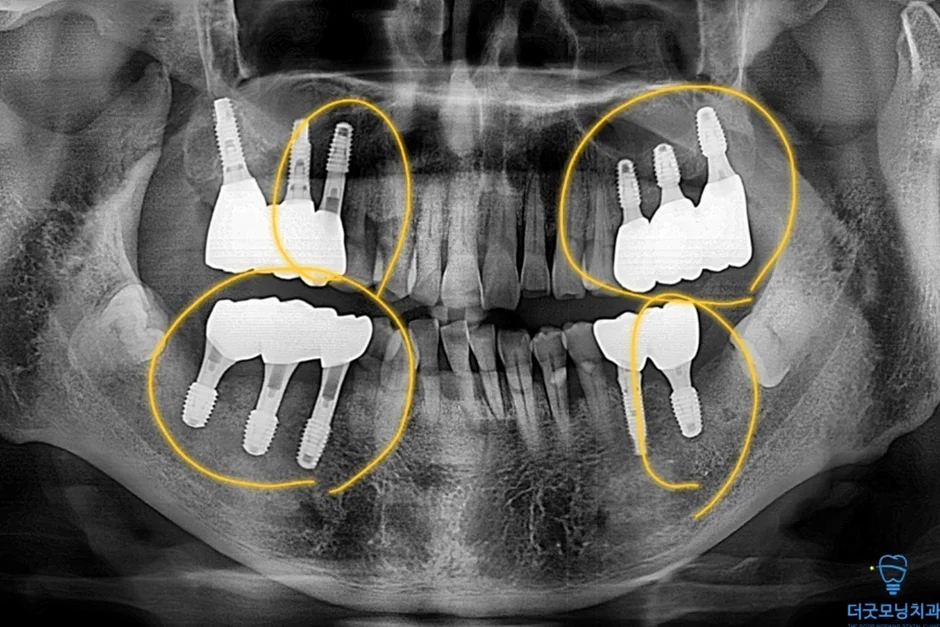

노란색 표시처럼 임플란트 식립 잘 마쳤습니다.

두 번째 수술에서도 임플란트가 CT 상에서 확인될 만큼 정확하고 안정적으로 식립되었습니다.